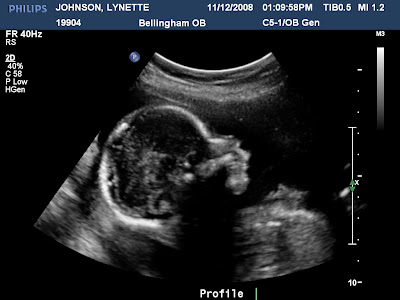

It's a boy....

So we had our 20 week ultrasound today and everything went well! Looks like Dylan will have a baby brother soon! He's not too sure about his baby brother yet.....Good thing he has another 4 months to get used to it! We are pretty sure the new little one will be named Gavyn. We are so excited for another little boy!